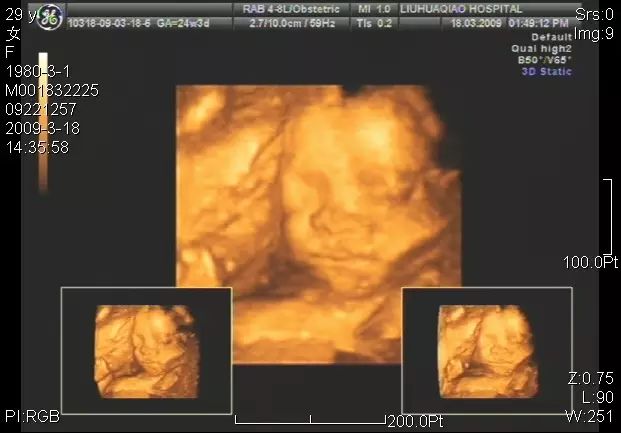

“大排畸”B超

孕18~24周进行一次详细、系统的超声检测,排除胎儿大部分畸形,因此也称作”大排畸”B超。这个时段胎儿的肢体及各主要脏器已经全部发育,而且羊水较适合做胎儿畸形筛查。

无论是二维、三维亦或四维彩超都只能对胎儿的大体结构进行筛查,也只有明显的结构畸形才能被发现。